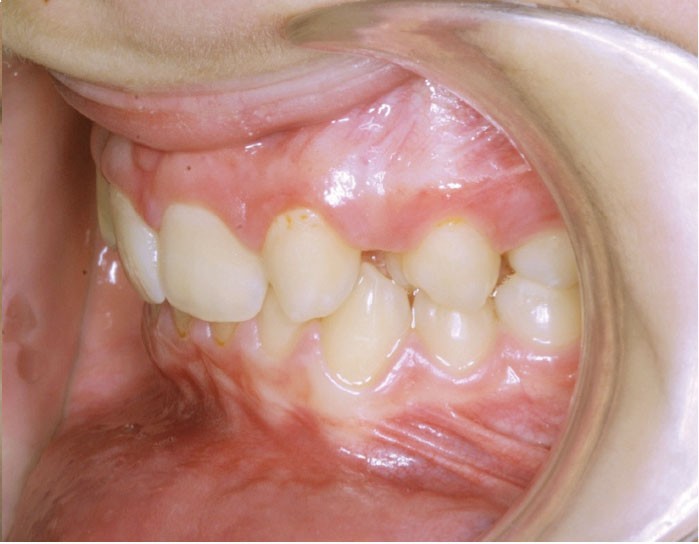

Les photographies de fin de traitement (fig. 4 et 5) montrent la préservation de l’équilibre facial et le respect du profil sous-nasal qui, malgré la croissance, ne s’est pas creusé. Le sourire est très harmonieux et révèle, comme les photographies endo-buccales, la très bonne intégration des canines substituées, après légère coronoplastie de leur pointe.

L’occlusion…